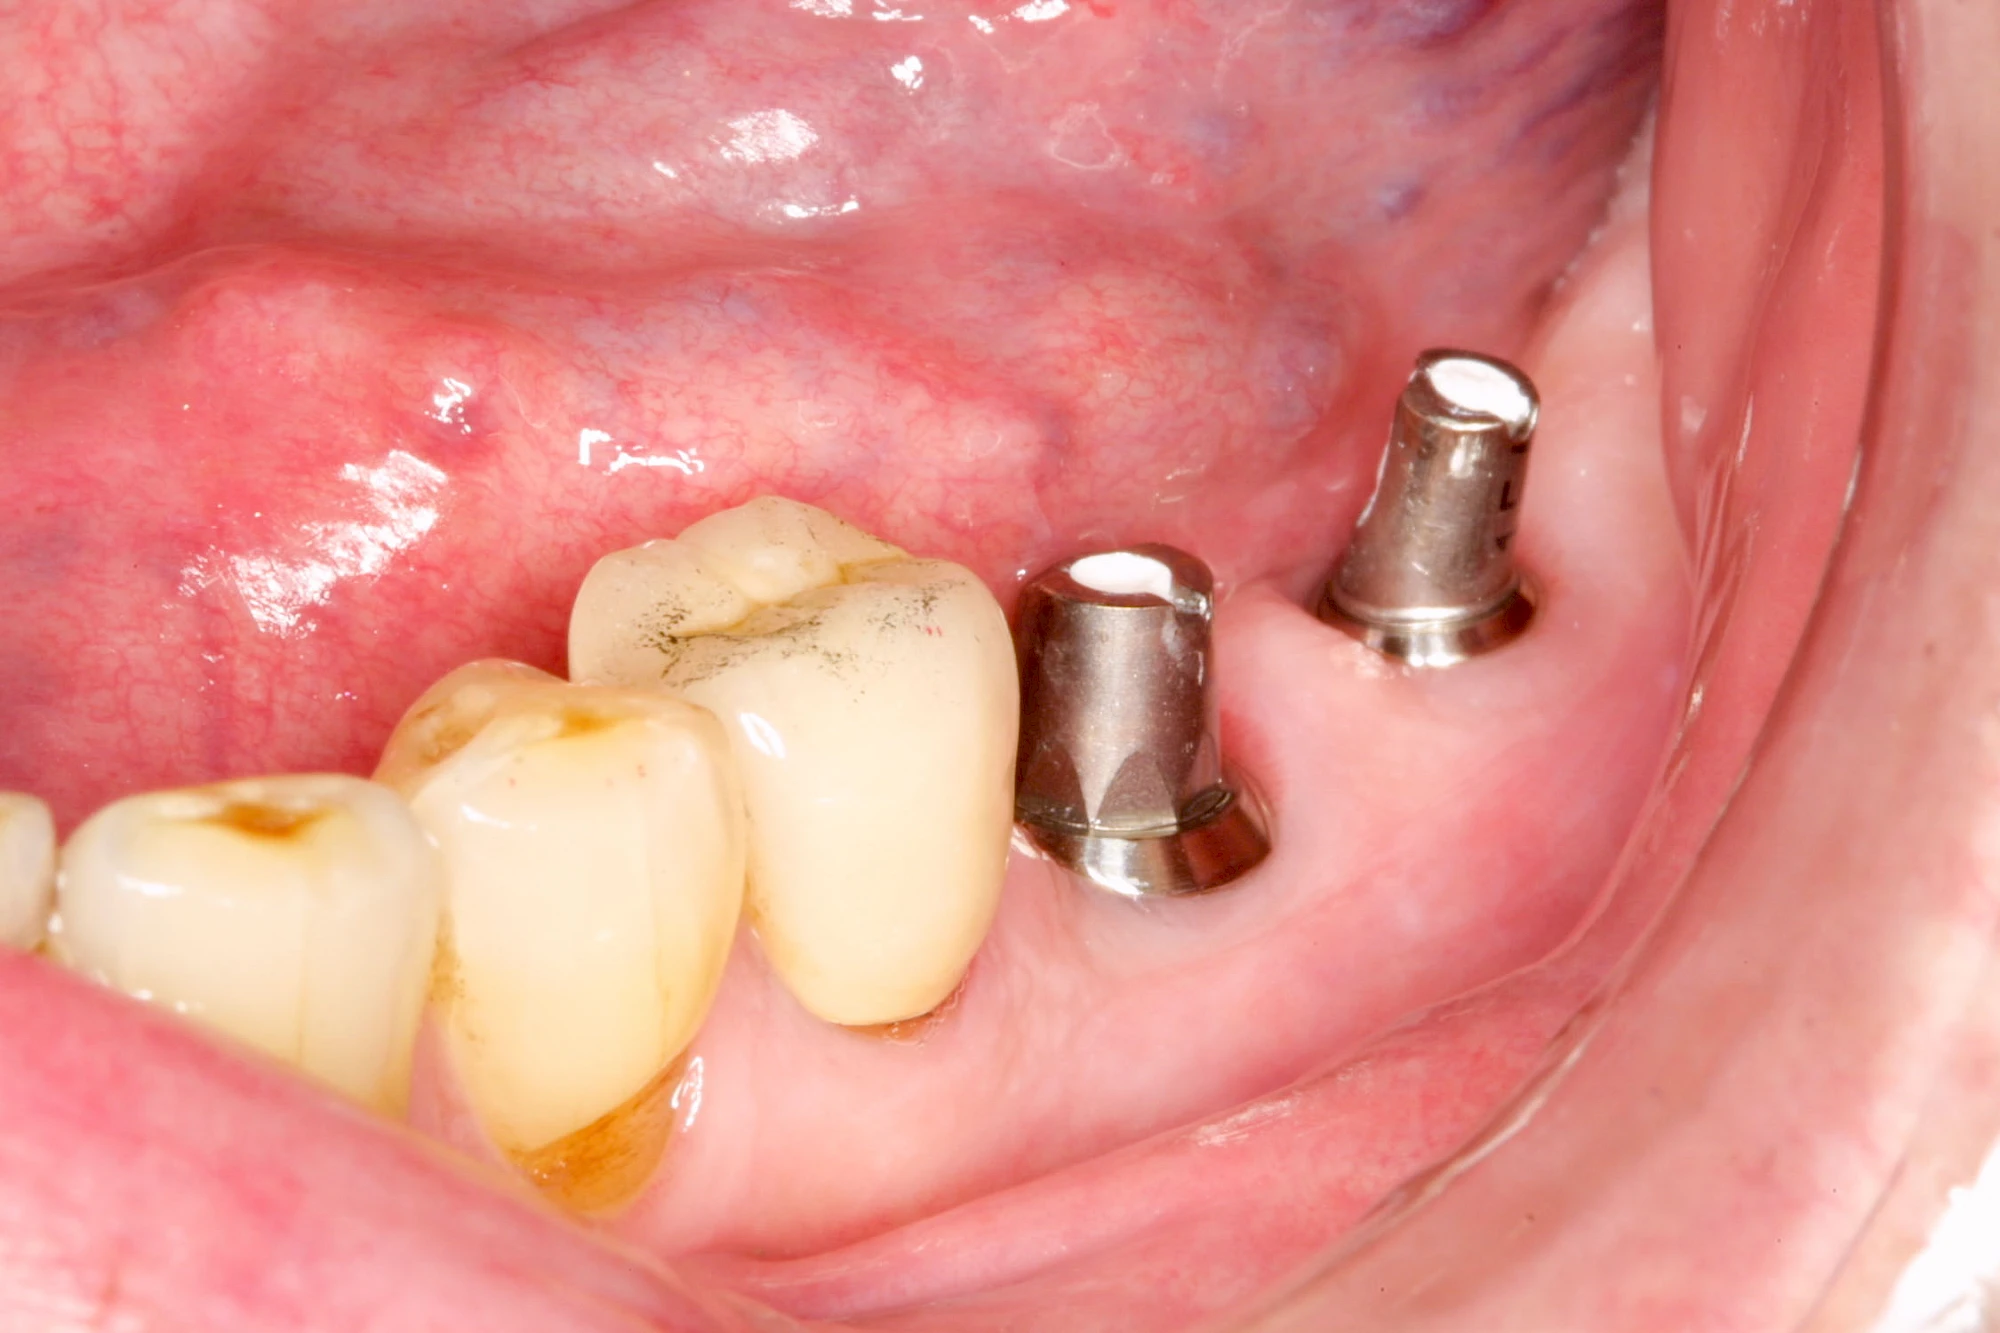

Implantate sind künstliche Zahnwurzeln. Nach einer gewissen Einheilzeit im Knochen (meist 3-6 Monate) erfolgt über einen separaten Aufbau (Abutment) die Befestigung einer Krone bzw. Brücke oder Zahnprothese.

In seltenen Fällen sind Implantate samt Aufbau aus einem Stück gefertigt. Auch gibt es Situationen, die ein Früh- oder sogar eine Sofortbelastung erlauben – dann kann die Einheilzeit der Implantate in den Knochen verkürzt oder sogar gänzlich darauf verzichtet werden.

Fehlen einzelne Zähne und die Nachbarzähne sind unbeschadet oder gut zahnärztlich versorgt, werden immer häufiger Implantate gewählt, um die Lücken zu schließen. Auch bei größeren oder verteilten Lücken, wenn keine herausnehmbare Prothese gewünscht ist, werden Implantate für Kronen- bzw. Brückenversorgungen gesetzt. In Einzelfällen entscheiden sich sogar zahnlose Patienten für eine festsitzende Versorgung auf Implantaten.

Varianten zur Verankerung von festsitzendem Zahnersatz auf Implantaten